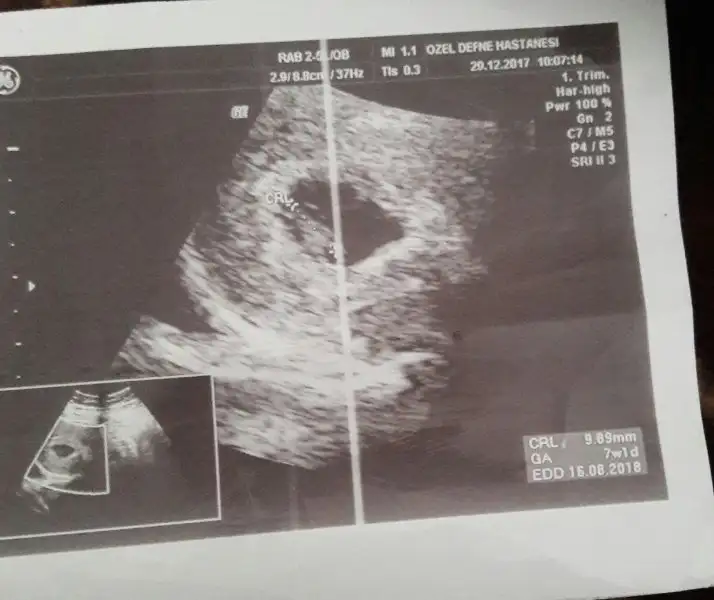

Doktorun tahminde bululnmadımıcanım sana zahmet varsa atabılırmısın tekrar kese konumu icin bu benımkıEki Görüntüle 2088211 buda 12haftalık usegEki Görüntüle 2088213

bır oncekı messjda arkadasa yazdımya 12.haftata yuksek ıhtımal kız dedı kese konumuna ınanmıyom dıyeDoktorun tahminde bululnmadımı